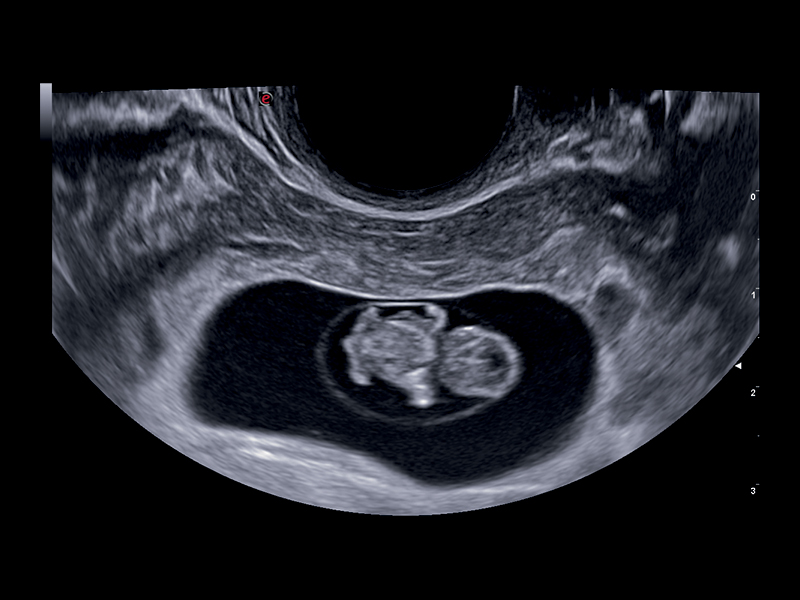

Seamless Image Quality

To ensure high-quality images from early pregnancy to birth, Esaote offers a wide range of probes, enabling end users to interrogate fetal anatomy with confidence and accuracy.

Recent technology embedded in the new C 2-9 high-frequency convex probe leverages a combination of advanced equipment, together with specifically designed transducer geometry, thus allowing the detection of the minute details of the fetus with outstanding image quality. Furthermore, the advanced image post-processing techniques help to increase clinicians’ diagnostic confidence and facilitate examination of fetal anatomy, from head to toe.

Clinical Images